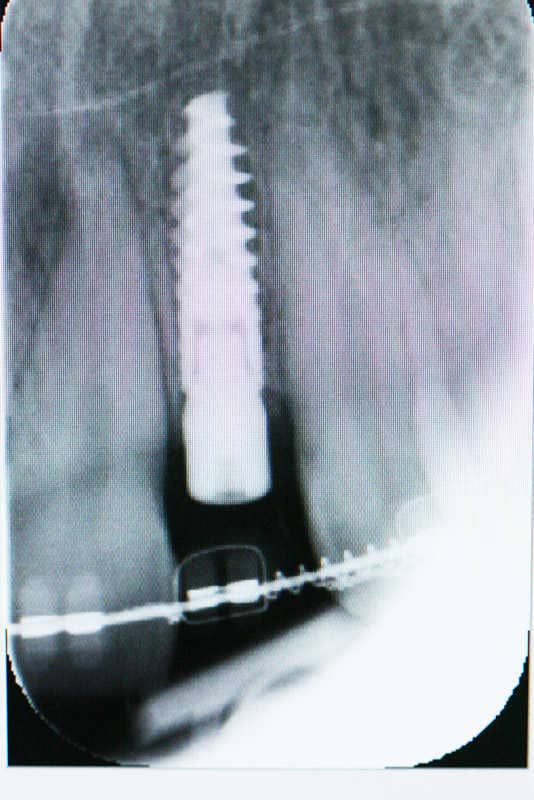

A rögzített fogszabályozó készülék levétele utáni állapot